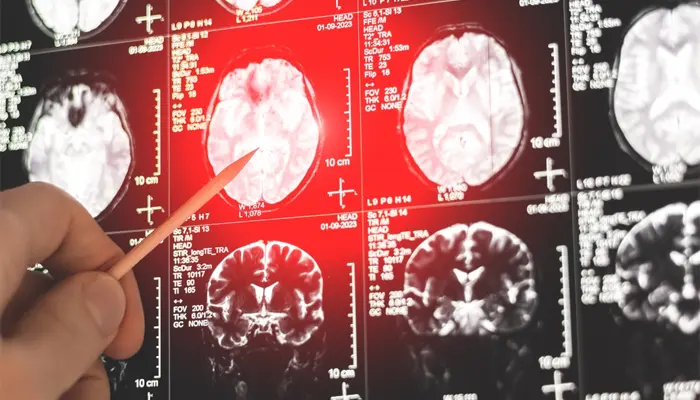

- Thiếu máu não

Thiếu máu não khiến lưu lượng máu lên não không ổn định, ảnh hưởng đến hoạt động của hệ thần kinh trung ương. Tình trạng này nếu kéo dài có thể gây rối loạn giấc ngủ, giảm khả năng tập trung, đau đầu, chóng mặt. Nhiều người bị thiếu máu não dù ngủ nhiều nhưng vẫn cảm thấy mệt mỏi, buồn ngủ liên tục, đặc biệt là vào ban ngày.

Ngủ nhiều nhưng vẫn buồn ngủ có thể dẫn đến thiếu máu não